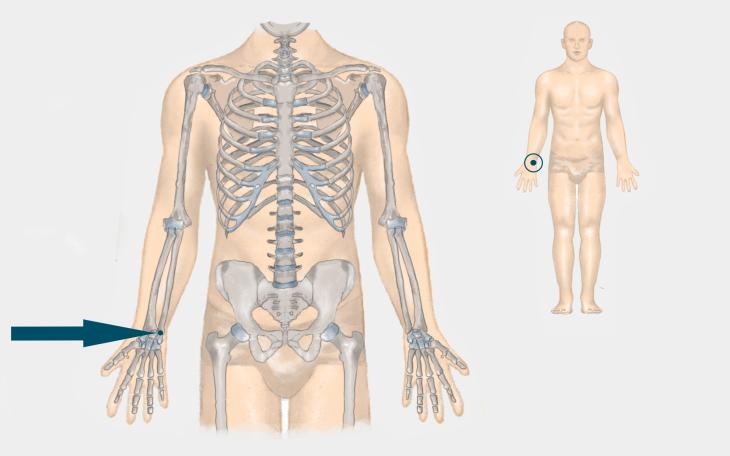

Die TFCC Läsion befindet sich zwischen der Elle und den Handwurzelknochen.